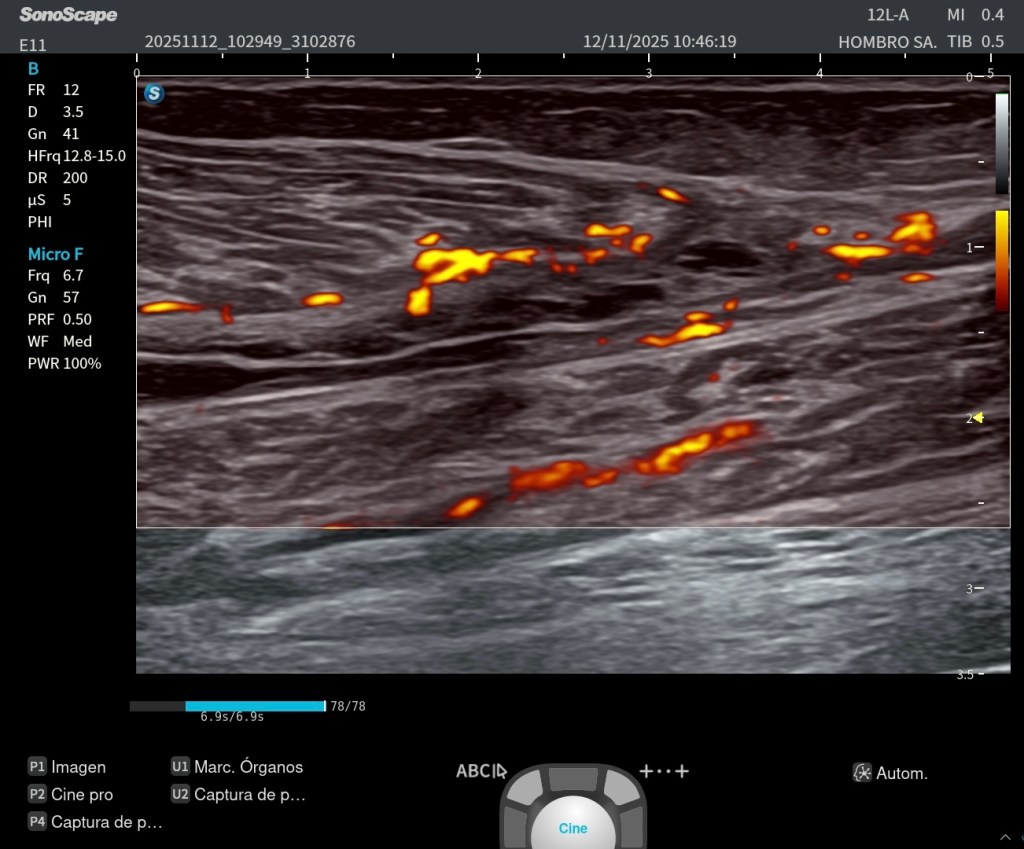

- Microvascularización intramuscular visible en modo Doppler en las fibras retraídas, indicativa de actividad reparativa.